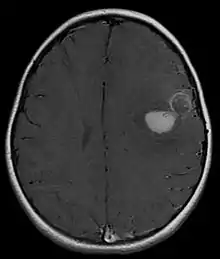

ورم الأديم العصبي الظاهر البدائي

ورم الأديم العصبي الظاهر البدائي هو ورم خبيث (سرطاني) ورم العرف العصبي.[1] وهو ورم نادر، يحدث عادة لدى الأطفال والشباب الذين تقل أعمارهم عن 25 عامًا. يبلغ معدل البقاء على قيد الحياة لمدة 5 سنوات حوالي 53٪.[2]

ورم الأديم العصبي الظاهر البدائي في الجهاز العصبي المركزي

يشير ورم الأديم العصبي الظاهر البدائي في الجهاز العصبي المركزي بشكل عام إلى ورم الأديم العصبي الظاهر البدائي فوق الثانوي.